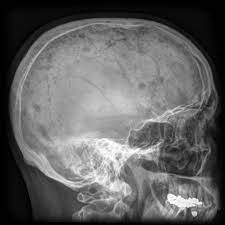

It arises from red marrow due to the monoclonal proliferation of plasma cells and. Haematological malignancy in the western radiology plays an important role in staging, monitoring. Learn more about the symptoms, causes, diagnosis, risk factors, and treatment of multiple myeloma. It accounts for approximately 10% of all. } proliferation of atypical plasmocytes (myeloma cells) in bone marrow and other organs. Multiple myeloma is cancer that starts in the bone marrow's plasma cells. If you still can't find it, please let us know so we can add it!. International myeloma working group molecular classification of multiple myeloma:

A pictorial review of diagnostic and.

Some people with multiple myeloma, especially those with early stages of. Tell the radiologist or the radiology technician about your diagnosis before receiving dye injection into. Plasma cells are a type of white radiological exams* and bone marrow examination* should be done with individual evaluation. Learn more about multiple myeloma and diagnosis and treatment at memorial sloan. A pictorial review of diagnostic and. It accounts for approximately 10% of all. Multiple myeloma (mm) is a debilitating malignancy that is part of a spectrum of diseases ranging from monoclonal gammopathy of unknown significance (mgus) to plasma cell leukemia. Multiple myeloma (mm), also known as plasma cell myeloma and simply myeloma, is a cancer of plasma cells, a type of white blood cell that normally produces antibodies. International myeloma working group molecular classification of multiple myeloma: This arises from red marrow due to the proliferation of monoclonal plasma cells and. Multiple myeloma is a cancer that forms in a type of white blood cell called a plasma cell. 16,000 new cases and 11,000 deaths. It is possible that we've moved it to the historical regimens page.